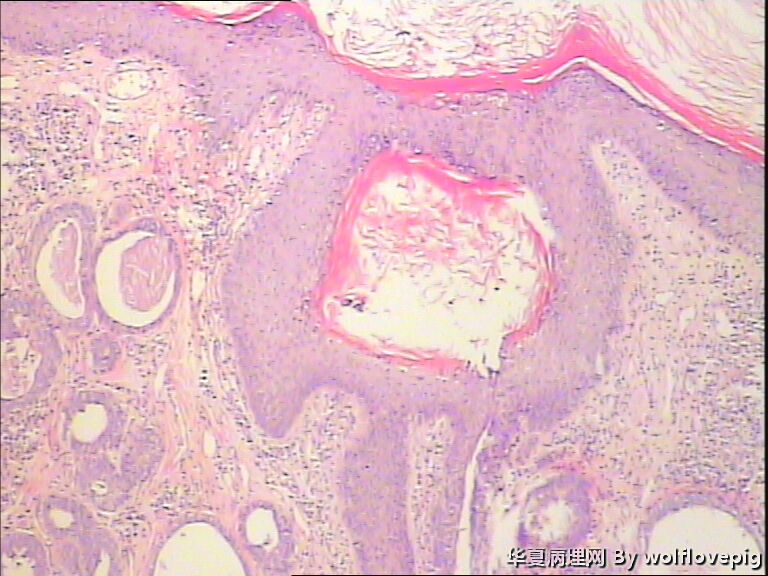

男,38y,腹部皮肤硬节20年。灰白不整形带皮组织一块:3.0*1.5*1.4cm,皮肤表面可见多个小结节样隆起。

我考虑1.皮肤混合瘤

2.乳头状小汗腺腺瘤

3.汗管瘤

考虑乳头状小汗腺腺瘤

支持乳头状小汗腺腺瘤。

常规病理改变考虑乳头状小汗腺腺瘤可能,需要免疫组化来进一步明确来源。

考虑毛囊瘤